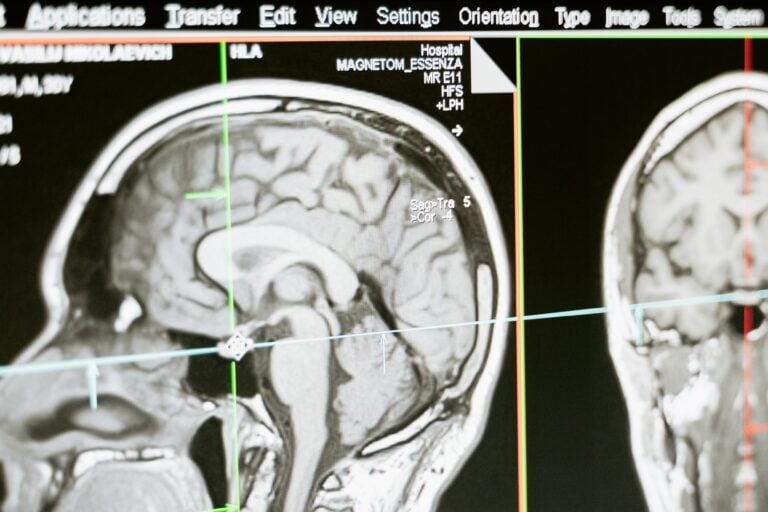

Tutkijat myöntävät, että kantasoluista tehty biologinen rakennelma muistuttaa enemmän sikiön kuin aikuisen aivorakennetta. Synapsien katoamisesta on silti saatu näyttöä ruumiinavauksissa ja magneettikuvauksissa. Havainto voi johtaa uusien hoitomuotojen kehitykseen.